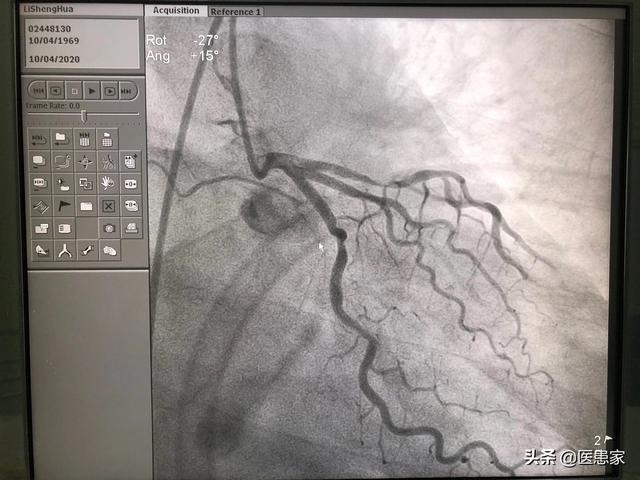

まず、冠状動脈狭窄のいくつかの大きな血管の狭窄が50%に達すると、冠状動脈性心臓病である;狭窄<50%、少なくとも冠状動脈アテローム性動脈硬化症に属し、冠状動脈性心臓病に発展する可能性があり、また積極的に制御する必要があります。冠動脈40%狭窄、高血圧、糖尿病、高脂血症などの基礎疾患の組み合わせのほとんどは、この時間は積極的に薬の血圧、血中脂質と血糖によって制御する必要があります。

心臓が血液を供給する動脈は冠動脈と呼ばれる。私たちが通常冠動脈性心臓病と呼んでいるものには、冠動脈の狭窄が50%以上という基準がある。冠動脈の狭窄が50%未満の場合は冠動脈アテローム性動脈硬化症と呼ばれる。